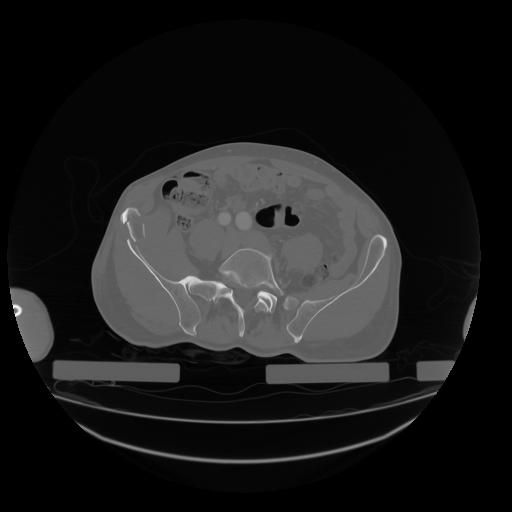

28 CUERPO,CE,Vol,2.0,CUERPO,,